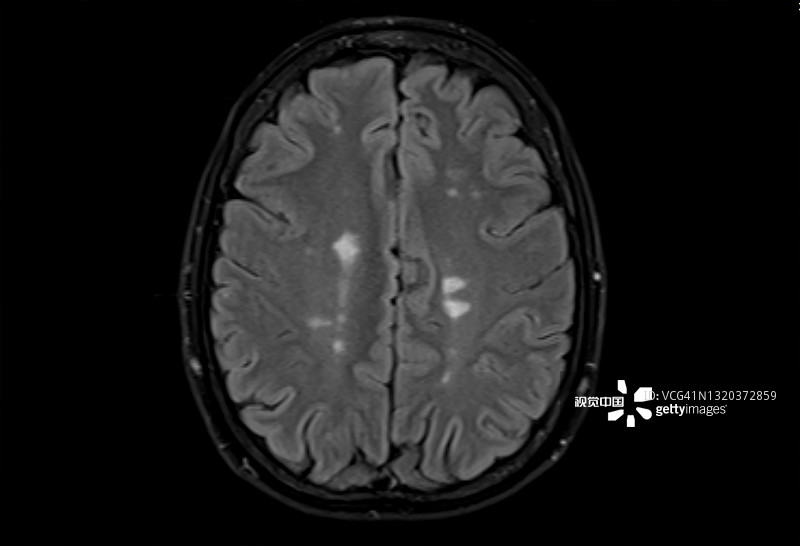

多發(fā)性腦硬化癥的磁共振成像,軸位Flair視圖